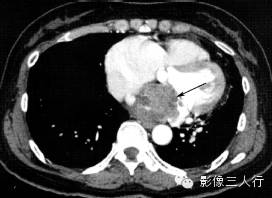

| 心房黏液瘤(图1) | 纤维瘤(图2) | 脂肪瘤(图3) | 横纹肌肉瘤(图4) | |

好发

年龄 |

成人 | 婴幼儿 | 成人 | 儿童或年轻人 |

部位 |

多起源于房间隔,以窄基底与其相连,并向心腔内生长 | 心室心肌内,常见于左室游离壁或室间隔 | 多原发于心外膜,在心房、心室无差异 | 各房室及间隔心肌壁均可发生,常累及一个以上心腔,可侵犯心包和大血管 |

病灶

形态 |

圆形或椭圆形,多呈浅分叶状,有蒂与心房间隔相连,肿瘤位置可随心动周期而变化,有时脱入左室 | 卵圆形或分叶状,常有薄层假薄膜,边界清楚 | 椭圆形或分叶状,边界清楚 | 形态不规则,边界不清,可见坏死、出血 |

CT

密度 |

稍低密度 | 密度稍低于心肌 | 脂肪密度 | 不均匀软组织密度 |

强化

特点 |

不均匀强化 | 强化程度较正常心肌弱 | 无强化 | 一般均匀强化,坏死后内部不强化 |